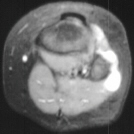

MRI examination of the left knee displayed a 2 cm. by 0.8 cm. lobulated

mass in the region of the common peroneal nerve with no enhancement (images

3and 4). On the T-2 weighted sequences there was abnormal increased signal

of the tibialis anterior, extensor digitorum longus and peroneus longus

muscle bellies suggesting atrophy (images 5, 6 and 7).